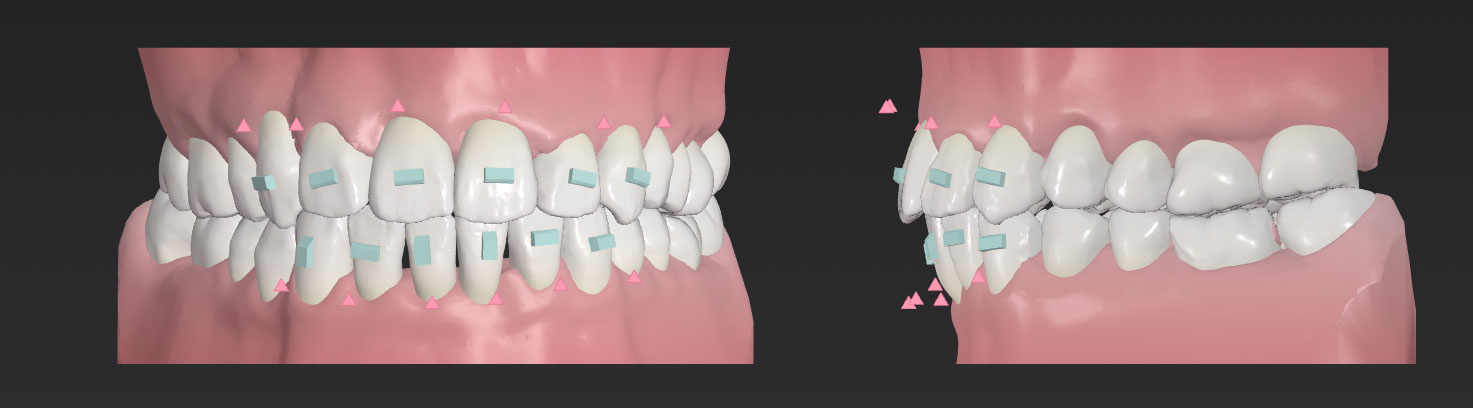

当院では、精密な3Dスキャンによるシミュレーションを行い、治療前に完成形の歯並びを確認します。その計画通りに歯が動いているかどうか、院長が毎回モニタリングしながら進めていきます。

当院では、精密な3Dスキャンによるシミュレーションを行い、治療前に完成形の歯並びを確認します。その計画通りに歯が動いているかどうか、院長が毎回モニタリングしながら進めていきます。

検査結果をもとに、治療のゴールや歯がどのように動いていくのかをシミュレーションします。マウスピース矯正では、3Dで動きを確認できるビジュアルシミュレーションをご覧いただけます。

矯正装置を装着したならば、定期的に受診していただきます。ワイヤー矯正の場合はブラケットやワイヤーの交換・調整、マウスピース矯正ではマウスピースのフィッティングや歯の移動の進捗状態を確認します。